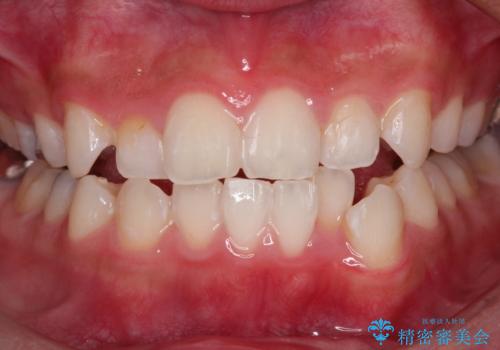

ワイヤー矯正中のクリーニング PMTC

- ワイヤー矯正中にクリーニングを行いたいとのことで来院されました。PMTC60分コースでと歯磨き指導も行いました。

ワイヤー矯正中はブラッシングが難しくなるため、磨き残しが多くなることがあります。適切な道具を使って、適切なブラッシング方法を習得することで、磨き残しを減らすことができます。

また、矯正で歯の移動があると今までなかったところに隙間が出てきたり、ガタつきが解消されてきたりすることで、お口の中の環境が変わります。そのため、定期的に専門的な機械・材料を使用したProfessinnalcleaning(pmtc)を行うことがおススメです。